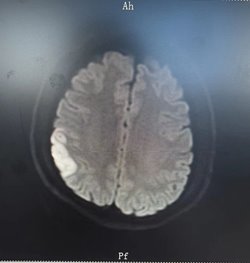

28岁的X先生一向身体健康,无烟酒不良嗜好,无高血压、糖尿病等基础疾病,但是3月前突然出现头晕、左侧肢体无力,伴有言语不清等急性脑梗死症状。于是急诊入住漯河市中心医院。头部磁共振平扫可见右侧额顶颞叶皮层及皮层下急性水肿性改变,提示急性脑梗死。但是磁共振动脉血管成像未见明显狭窄或阻塞。